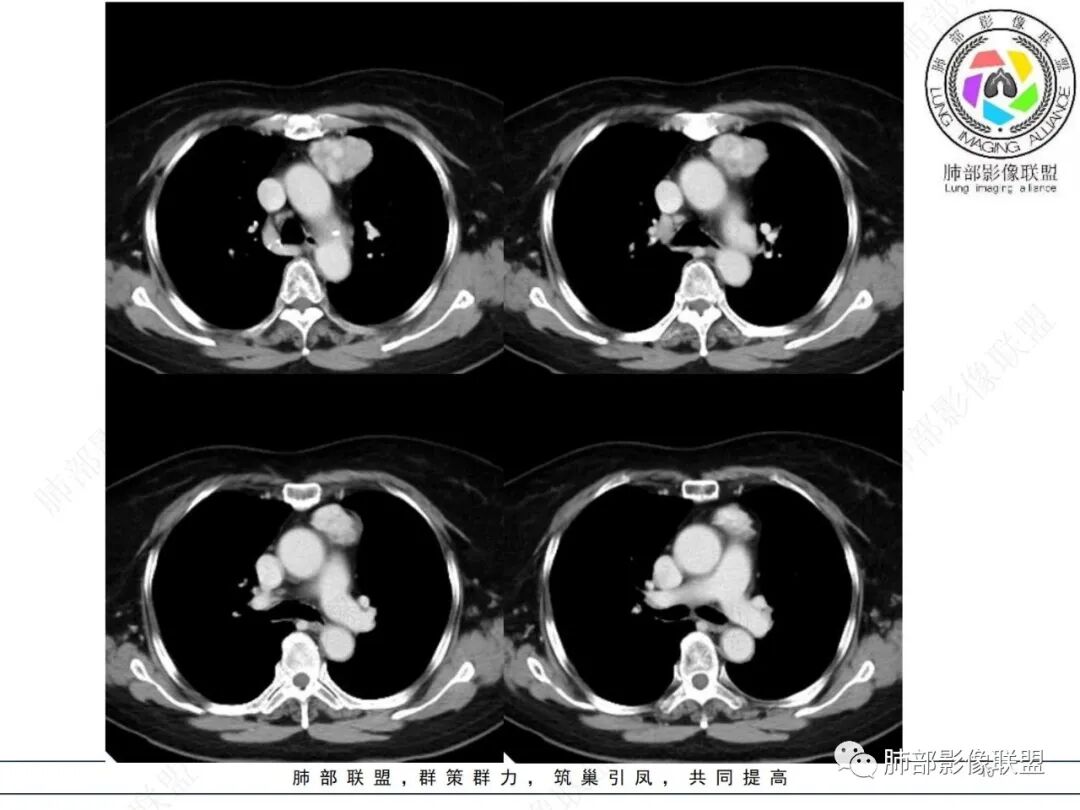

前上纵隔偏左侧实性病灶,边界清楚,边缘彭隆,浅分叶,内部密度均匀,未见钙化、脂肪密度,周围脂肪间隙清晰。

包膜完整,纤维分隔,结节感明显

平扫密度较均匀,增强渐进性不均匀强化,内见低密度纤维分隔。未见肿大淋巴结。未见胸腔积液。

肿块边界清楚,低密度纤维间隔,未见侵犯转移及增大淋巴结,多见于胸腺瘤AB型

—强化程度及强化方式不支持常见的血管瘤及巨淋巴结增生症(CD)。